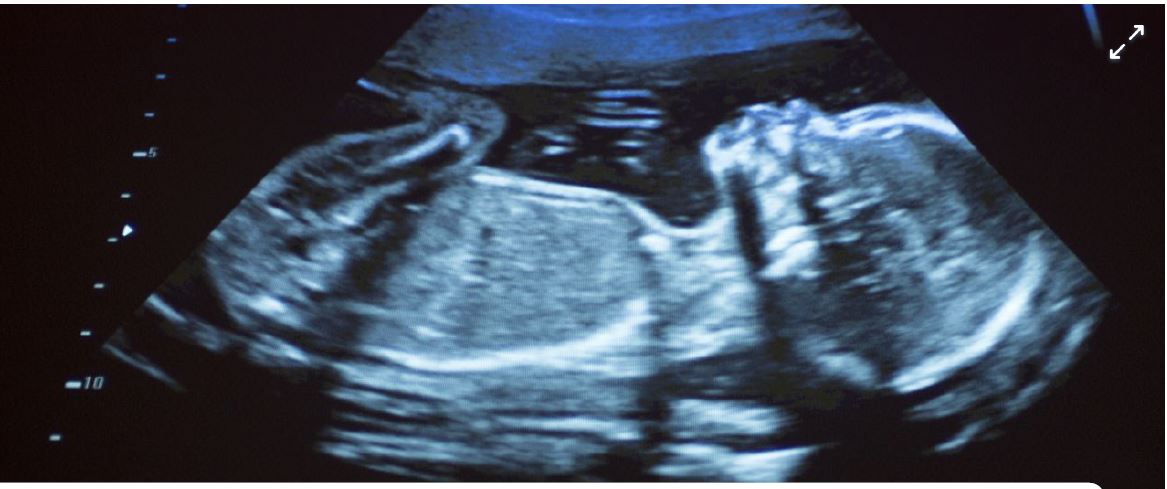

Research undertaken by scientists at Hasselt and Aberdeenuniversities reveals that traces of air pollution are present in the vital organs of unborn babies. Prof Tim Nawrot points to earlier research by his team that showed the presence of soot particles in all stages of pregnancy. The present research confirms the particles also enter the foetus’s organs. The soot particles in the air mainly originate from the burning of fossil fuels like diesel and heating fuel. In the past studies have shown the negative impact these particles can have on everybody’s health including that of the unborn.

Research conducted in Hasselt in 2019 revealed the presence of soot particles in the placenta during the early stages of pregnancy. “At twelve weeks we discovered soot particles on the mother’s side and on that of the foetus,” says Nawrot. Concentrations were highest on the foetus’s side. Researchers now wanted to establish the exact impact of soot particles in foetus development in the womb. The scientists discovered soot particles finding their way to the liver, the lungs and even the brain at a time when these vital organs are in full development. Prof Paul Fowler of Aberdeen University is particularly concerned about the presence of soot particles in developing brains. Exposure to air pollution during pregnancy has been linked to still and premature births, poor weight and disrupted brain development. The researchers say their work underpins the need to limit soot discharges because of the role it can play in the early stages of human development.